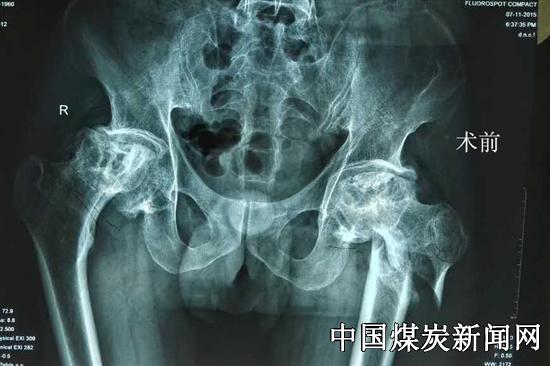

一名50多岁的男性武姓患者,因摔伤导致粗隆下粉碎性骨折伴有股骨头坏死10余年,影响该患者长期股骨头坏死造成髋臼底骨质菲薄,用普通生物髋臼容易造成术后松动,考虑到患者症状,峰峰集团总医院邯郸院区骨四科主任王晖带领团队经过缜密研究,决定利用高科技3D打印给其私人订制髋关节来准确手术。

3D打印人工髋关节的最大特点在于臼杯,3D打印的臼杯及其微孔表面是一体成型,医生将检查的影像数据传给3D打印部门,工程人员再将数据通过软件分析重建成三维立体,按照设定的形状,把预先放入工作舱中的钛合金粉一层层堆积制造,最终打印成型。骨四科主任王晖采取“骨小梁3D打印髋臼”的技术,改善通用器械对复杂病例的处理局限。通过精确的3d打印技术来保证对患者进行全髋关节置换手术准确操作,患者术后早期就可下地行走。3D打印技术应用在髋关节置换上的应用,可有效解决了髋关节翻修、DDH畸形、粗隆间粉碎性骨折等疑难病症,减轻患者的痛苦,减少假体松动和术后并发症,提高了手术的成功率。